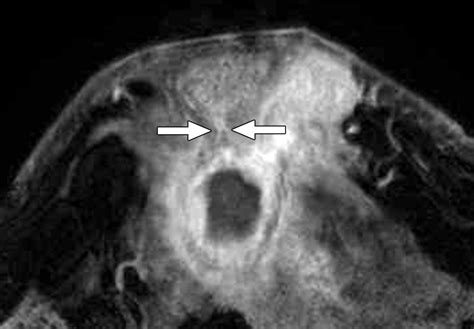

Absceso Subareolar

Un absceso subareolar es una acumulación de pus en la glándula areolar, ubicada en la mama debajo de la areola. Este absceso es causado por un bloqueo de las pequeñas glándulas o conductos bajo la piel de la areola, lo que provoca una infección en dichas glándulas. Este problema es poco común y afecta a mujeres jóvenes o de mediana edad que no están amamantando. Los factores de riesgo incluyen diabetes, perforaciones en los pezones y tabaquismo.

Los síntomas de un absceso areolar son:

- Una protuberancia sensible e hinchada debajo del área areolar, con hinchazón y calentamiento de la piel sobre dicha área

- Drenaje y posible pus procedente de esta protuberancia

- Fiebre y escalofríos

- Malestar general o fatiga

El tratamiento incluye antibióticos y el drenaje del tejido infectado, que puede realizarse en un consultorio médico con anestesia local. Si el absceso reaparece, las glándulas afectadas deben extirparse quirúrgicamente.

La zona roja, caliente y dolorosa que había inicialmente en el pecho, se muestra ahora dura externamente, pero fluctuante a la palpación, con la piel muy roja tensa y brillante.

La ecografía puede resultar útil en el diagnóstico y tratamiento del absceso mamario. Es posible puncionar con aguja guiada por ecografía y colocar un catéter de drenaje con buen resultado.